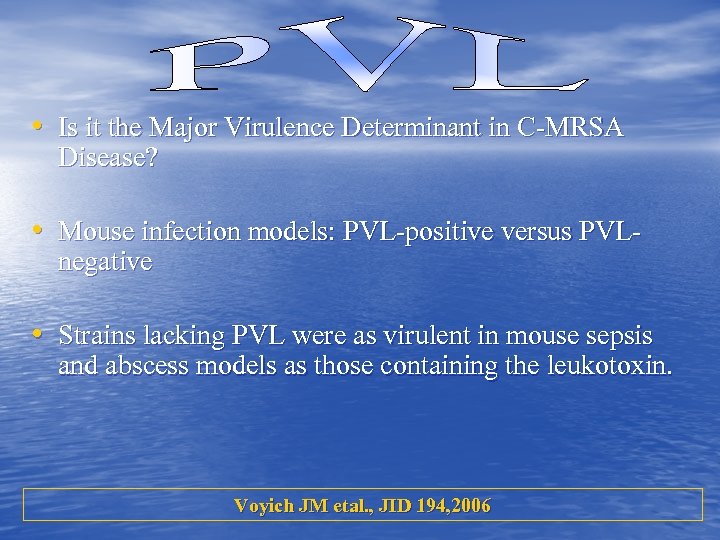

• Is it the Major Virulence Determinant in C-MRSA Disease? • Mouse infection models: PVL-positive versus PVLnegative • Strains lacking PVL were as virulent in mouse sepsis and abscess models as those containing the leukotoxin. Voyich JM etal. , JID 194, 2006

• Is it the Major Virulence Determinant in C-MRSA Disease? • Mouse infection models: PVL-positive versus PVLnegative • Strains lacking PVL were as virulent in mouse sepsis and abscess models as those containing the leukotoxin. Voyich JM etal. , JID 194, 2006

v. PVL-negative strains were as lethal as wild-type strains in a sepsis model, and they caused comparable skin disease. Voyich JM etal. , JID 194, 2006

v. PVL-negative strains were as lethal as wild-type strains in a sepsis model, and they caused comparable skin disease. Voyich JM etal. , JID 194, 2006